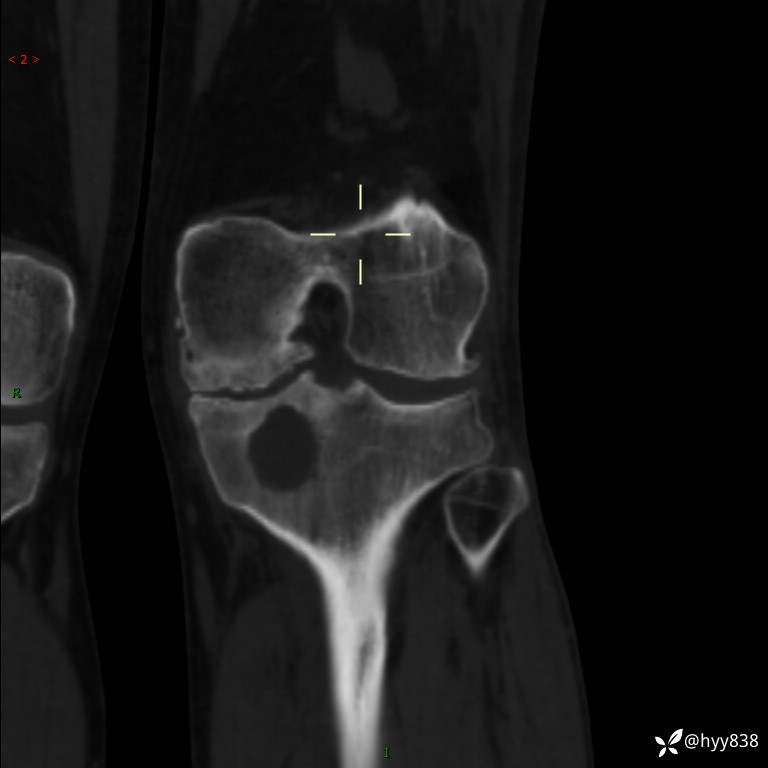

CT